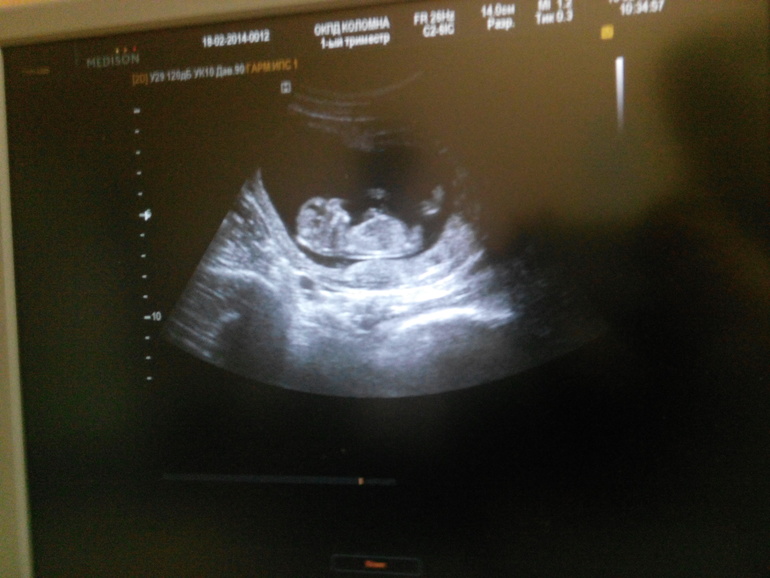

По УЗИ все в норме. Ребенок один. Я специально ее переспросила, а то уж больно неразговорчивая узистка. Руки-ноги есть. Сам плод 57 мм. ЧСС 166. Соответствует 12 неделям и 2м дням. По М 13 недель, как и показывает ББ. Пол не определила, хоть и пыталась, положение неудачное для этого (она действительно профессионал, никогда не слышала, что б Рыбакова ошиблась).

Ничего особо не сказала и даже не показывала,повезло, что последняя картинка осталась на экране и я даже успела кое-как сфоткать)